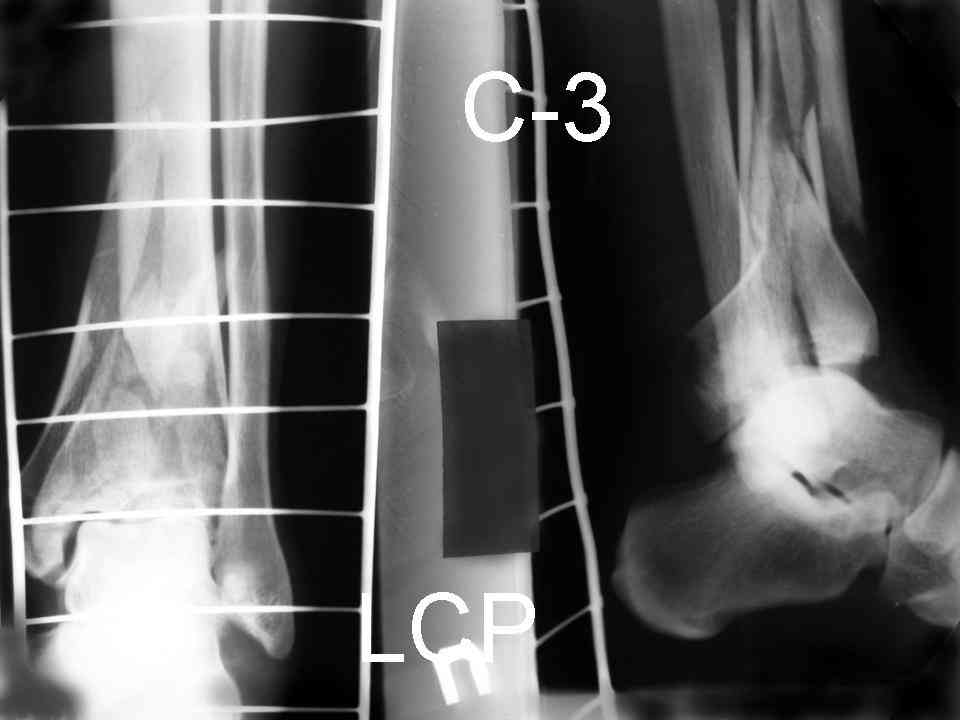

Ещё есть одна проблема когда есть перелом малоберцовой кость, то всё ясно. А когда малоберцовая кость не повреждена, то сразу накладывается аппрат наружной фиксации при поступлении, чтобы как бы перерастянуть отломки и главное убрать вальгусное или варусное смещение, а потом на 5-7 день открыто большеберцовая кость восстанавливается и фиксируется пластиной. С уважением Дрягин

Посылаю результат лечения предыдущего больного через год.

С уважением Дрягин